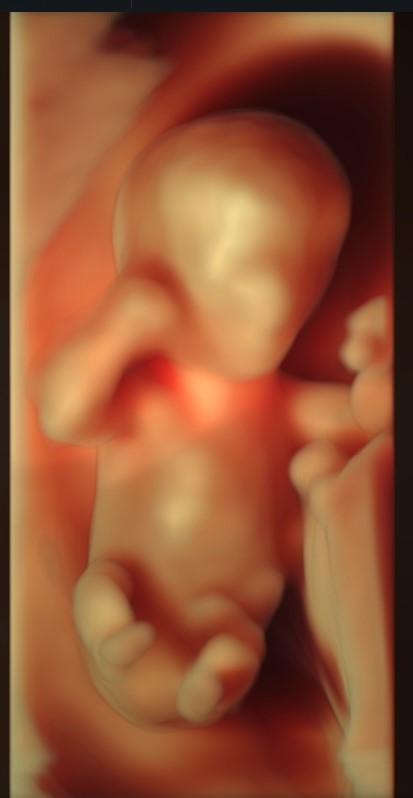

• ultrazvukové vyšetrenia gynekologické a tehotných